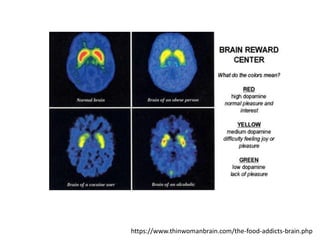

http://makeyourbodywork.com/overcoming-sugar-addiction/

https://www.thinwomanbrain.com/the-food-addicts-brain.php